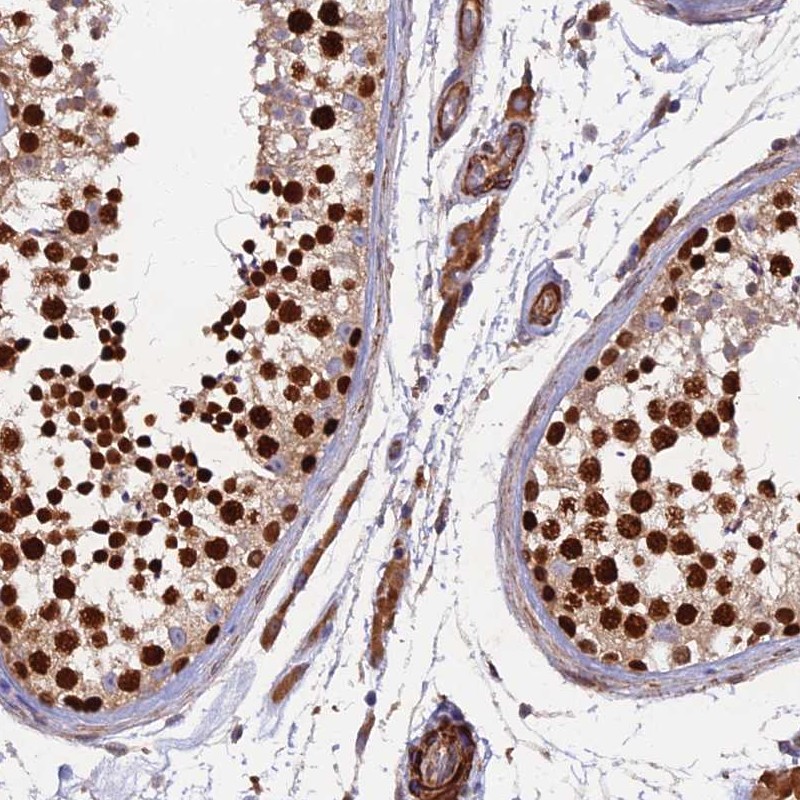

Immunohistochemical staining of human testis shows nuclear and cytoplasmic positivity in cells in seminiferous ducts.